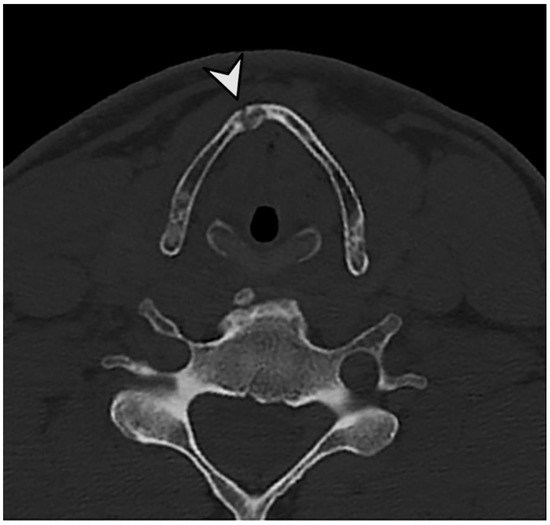

3.3. Evaluation of Specific Cases

3.4. Detailed Findings